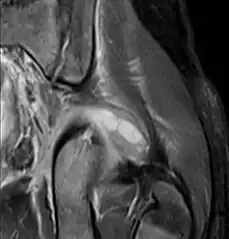

| Transverse T2 magnetic resonance imaging section through the hip region showing abscess collection in a patient with pyomyositis. | |